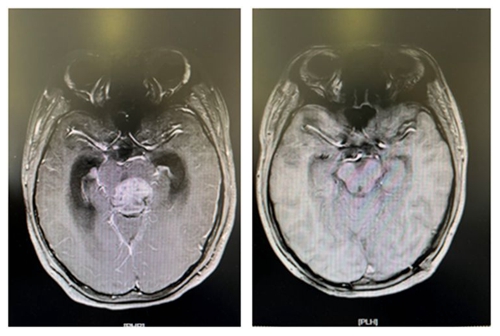

术前肿块影像                                                术后全切影像

据了解,患儿小周今年11岁,因突发头痛呕吐、视物模糊前往医院就诊。到医院检查得知小周颅内松果体区长了一个鹌鹑蛋大小的肿瘤,并且已造成梗阻性脑积水,颅内高压,若不及时处理,随时有生命危险。医院神经外科王知非教授团队在接诊的首日就为患儿行急诊脑室外引流术缓解症状以便争取时间,随即为患儿制定手术方案。4月8日,王知非教授团队在全麻插管下为患儿行松果体肿瘤切除术,术后,患儿头痛呕吐视物不清等症状均好转,无任何功能障碍。